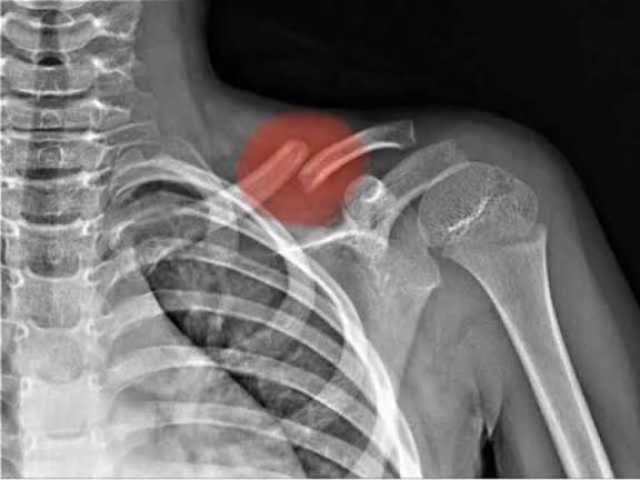

ما الذي يحدث عند كسر الترقوة؟كيف يتم تشخيص كسر الترقوة؟

يبدأ التشخيص بفحص سريري يتبعه تصوير بالأشعة السينية لتحديد:

ـ مكان الكسر

ـ نوعه

ـ مدى انفصال الأجزاء

وفي الحالات المعقدة يستخدم الأطباء الأشعة المقطعية قبل وضع خطة العلاج.